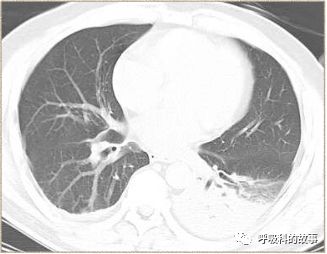

于是众人在吴主任的指挥下忙碌起来,胸部CT回报左下肺大片实变影。脑脊液生化示蛋白(脑脊液) 42.2mg/dl,葡萄糖(脑脊液) 6.75mmol/L,氯化物(脑脊液) 125mmol/L;脑脊液常规潘氏试验 阴性,脑脊液红细胞 5/μl,脑脊液有核细胞 1/μl。

“看来,至少脑膜炎可以排除,而肺炎成立。我们感染性疾病的诊治的第一关---感染部位解决了。”吴主任稍微松了口气。